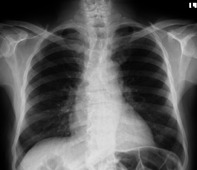

Case presentation: A 69-year-old male was referred to Tikur Anbessa Specialized Hospital (TASH) with obstructive lower urinary tract symptoms (LUTS) lasting seven months. He had previously undergone transurethral resection of the prostate (TURP), with histopathological findings suggestive of benign prostatic hyperplasia (BPH). Further investigation revealed an extremely elevated PSA level of 1768 ng/ml. Magnetic Resonance Imaging (MRI} raised high suspicion for locally advanced prostate cancer; however, a repeat biopsy and histopathology ultimately diagnosed TB prostatitis. The patient responded successfully to anti-tuberculosis therapy.